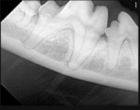

SOPIX är en DR sensor med kabel som kopplas i USB kontakten på er dator. Sensorn finns i storlekarna Size 1 (25x39mm) och Size 2 (31x42mm).

Size 1 är lämplig för katt och Size 2 för hund.

Sensorerna har en väldigt hög synbar upplösning tack vare en speciell fiberteknik, supersmå pixlar och känslig scintillator (lagret som omvandlar röntgen till elektronisk läsbart ljus). Pixlarna är endast 20um stora vilket ger en teoretisk upplösning på 25lp/mm. Kabeln är hela 370cm lång (70cm som inbyggd i Xmind Unity röntgenapparaten).